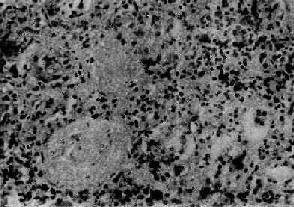

图12-22弥漫性硬化性肾小球肾炎

肾小球纤维化,玻璃样变;肾小管也大部分萎缩纤维化;间质纤维组织增生,有多数慢性炎细胞浸润